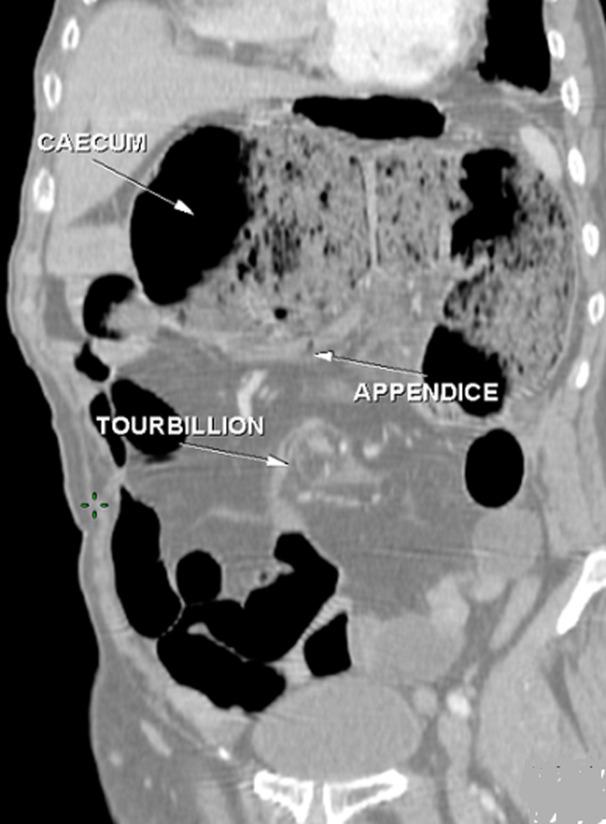

Emergency diagnosis of small bowel volvulus can be established in patients with acute intestinal obstruction, or even shock, or repeated abdominal pain often associated with motility disorders. This is a life-threatening complication of common incomplete mesentery, which is defined as an intestinal malrotation occurring very rarely in adults. Clinical symptoms are non-specific, hence the importance of knowing the radiological features, in particular scannographic features of this rare entity, thus enabling early therapeutic management. We here report the case of a 65-year-old patient admitted with total small bowel volvulus complicating common incomplete mesentery, diagnosed based on abdominal computed tomography (CT) scan and confirmed at surgery, who had favorable outcome.

对于患有急性肠梗阻甚至休克的患者,或经常伴有运动障碍的反复腹痛患者,可作出小肠扭转的紧急诊断。这是常见的肠系膜不完全性扭转的一种危及生命的并发症,其定义为成人中极为罕见的肠旋转不良。临床症状不具有特异性,因此了解这种罕见病症的放射学特征,尤其是扫描特征非常重要,这样才能进行早期治疗管理。我们在此报告一例65岁患者,因全小肠扭转并发常见的肠系膜不完全性扭转入院,通过腹部计算机断层扫描(CT)确诊,并在手术中得到证实,患者预后良好。